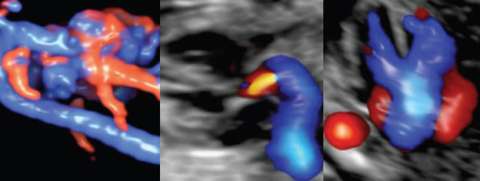

The Afshar lab is a translational laboratory integrating cutting edge prenatal maternal-fetal imaging, underlying genetic predispositions, and environmental clues to understand congenital heart disease and the placenta-cardiac axis. The laboratory seeks to understand the upstream and downstream signaling alterations in congenital heart disease and the placenta to define what we have termed the prenatal vascular phenotype.

The Prenatal Vascular Phenotype and Fetal Congenital Heart Disease

Congenital heart defects (CHDs) are the most common cause of congenital anomaly, occurring in ~1% of newborns. These neonates generally survive in-utero; however, there is lifetime morbidity related to vascular sequalae. The etiology(ies) of CHD remain elusive making intervention purely mechanical. Upstream and/or downstream signaling alterations in endothelial mechano-transduction throughout their life due to the abnormal flow patterns, remains a unifying phenotype. We have termed this the prenatal vascular phenotype.

To understand and target the mechanisms underlying the vascular phenotype, we aim to integrate data through the life course -- the prenatal and postnatal sequalae. We couple prenatal maternal-fetal imaging, underlying genetic predispositions, and developmental endothelial flow dynamics. Ultimately, this may improve treatment that arise from loss of vascular integrity. Despite being born with a morbid CHD, we have a chance to understand downstream complications and interventions that can improve quality of life in these patients with lifelong sequelae related to an abnormal endothelial cell and vascular phenotype.